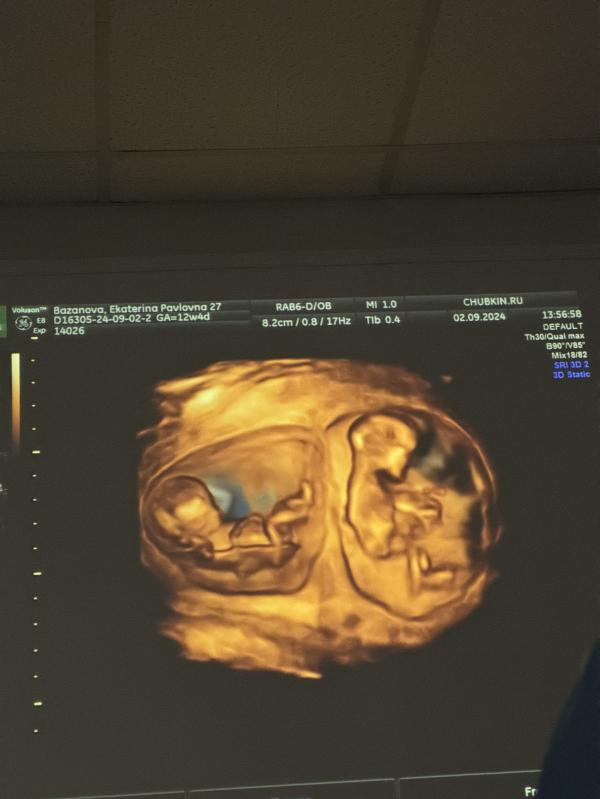

Вот такие красивые и большие♥️

Подскажите , где делали узи ?)

В клиники плода и мамы доктора Чубкина (конкретно у Чубкина)